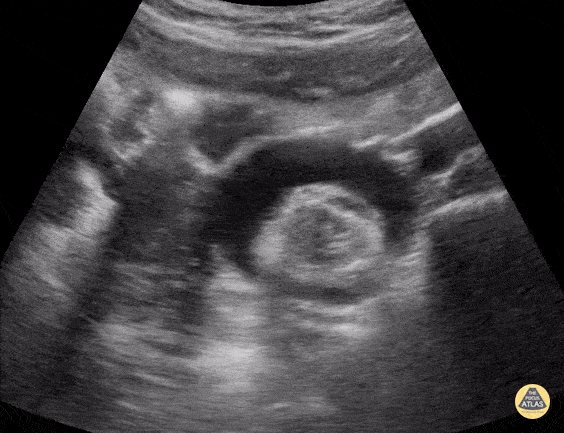

16 year old female with abdominal/pelvic pain. POCUS demonstrated bilateral ovarian teratomas. Shown here is a transverse pelvic view at the level of the uterine fundus focused in the L adnexa. A large complex mass with mixed hypoechoic and hyperechoic content is seen in the L adnexa, and a second similar-appearing mass can be partially seen in the R adnexa. Contributor: Matthew Moake, MD PhD